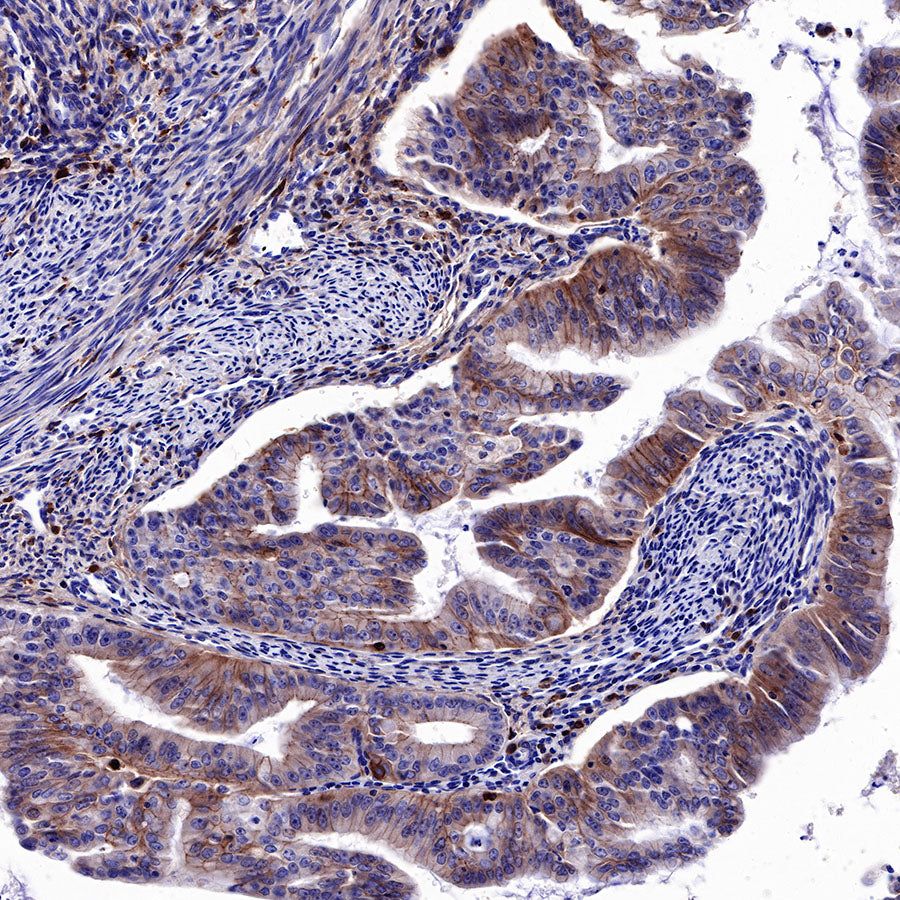

IHC shows positive staining in paraffin-embedded human colon. Anti-EGFR antibody was used at 1/2000 dilution, followed by a HRP Polymer for Mouse & Rabbit IgG (ready to use). Counterstained with hematoxylin. Heat mediated antigen retrieval with Tris/EDTA buffer pH9.0 was performed before commencing with IHC staining protocol.

IHC shows positive staining in paraffin-embedded mouse colon. Anti-EGFR antibody was used at 1/500 dilution, followed by a HRP Polymer for Mouse & Rabbit IgG (ready to use). Counterstained with hematoxylin. Heat mediated antigen retrieval with Tris/EDTA buffer pH9.0 was performed before commencing with IHC staining protocol.